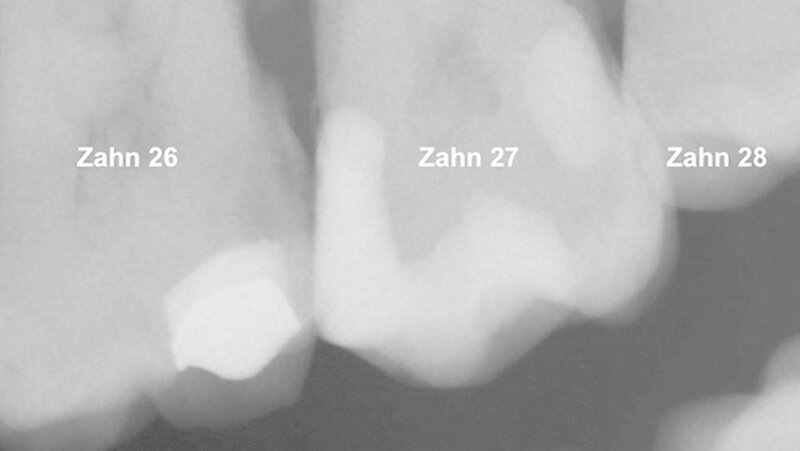

Ein 72-jähriger Patient stellte sich im Oktober 2013 zu einer Routinekontrolle in der Poliklinik für Zahnerhaltung und Parodontologie der Universität Regensburg vor. Bei der Befunderhebung wurde aufgrund des Verdachts auf Approximalkaries eine Röntgenaufnahme im Bereich des zweiten Quadranten angefertigt. Im Bereich des Zahns 26 distal wurde eine "Caries profunda“ diagnostiziert (Abbildung 1) und daher ein Termin zur Füllungstherapie vereinbart.

Der Patient berichtete über keine postoperativen Hypersensitivitäten nach der Behandlung. Die Röntgenaufnahme zeigt eine dichte Adaption von Biodentine an das Dentin, wobei aufgrund der ähnlichen Röntgenopazität von Dentin und dem Material eine Diskriminierung zwischen den beiden Schichten nicht leicht ist (Abbildungen 9 und 10).

Bezüglich einer reaktiven Reizdentinbildung, wie sie in der Literatur ebenfalls für das Produkt angegeben wird [Septodont R&D, 2010], lässt sich in diesem Fall auf der Basis der Röntgenbilder keine Aussage treffen.

Daher wurde im vorliegenden Fall das Material aufgrund seiner biologischen Aktivität einerseits und der dentinähnlichen mechanischen Eigenschaften andererseits als Unterfüllungsmaterial eingesetzt. Klinisch zeigte sich dabei, dass sich der Kalzium-Silikat-Zement gegenüber anderen Materialien zur Cp-Behandlung aufgrund seiner Konsistenz nach dem Anmischen ohne Druck aufbringen sowie dicht an das Dentin adaptieren lässt und nach der Abbindung eine mechanisch stabile Barriere darstellt. Dies zeigt auch die Röntgenaufnahme nach sieben Monaten. Ein zweizeitiges Vorgehen war im vorliegenden Fall nicht indiziert.